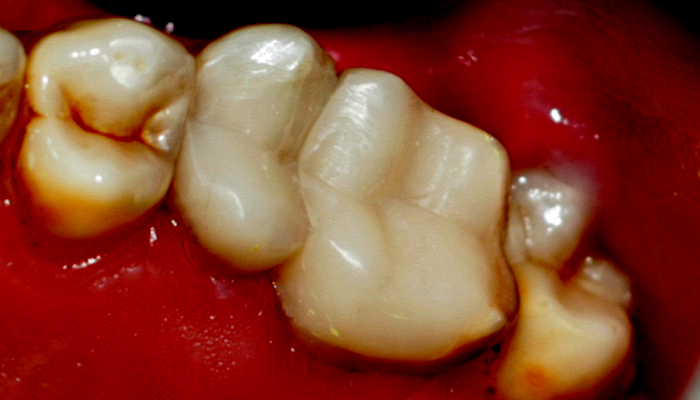

Ендодонтията е раздел от съвременната дентална медицина, който раздел изучава физиологията и патологията на вътрешната част на зъба - пулпна кухина и коренови канали. Названието на раздела идва от старогръцки - ендос - представка за вътрешност и одонтос - зъб. Това е една от научните дисциплини, които претърпяха голямо развитие през последното деситилетие.